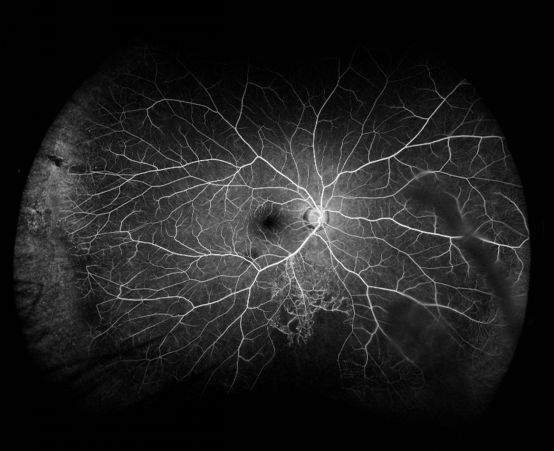

在单次拍摄中,图像至少包括四个涡静脉壶腹(视网膜接近远周部的结构性

同时,欧堡超广角成像技术,无需散瞳,单次成像轻松获取涡静脉甚至赤道

即,一张正位图片上至少要看到4个涡静脉范围的图像才能称之为超广角

允许一次扫描即可获得广达200°的眼底成像,轻松获取涡静脉以前图像